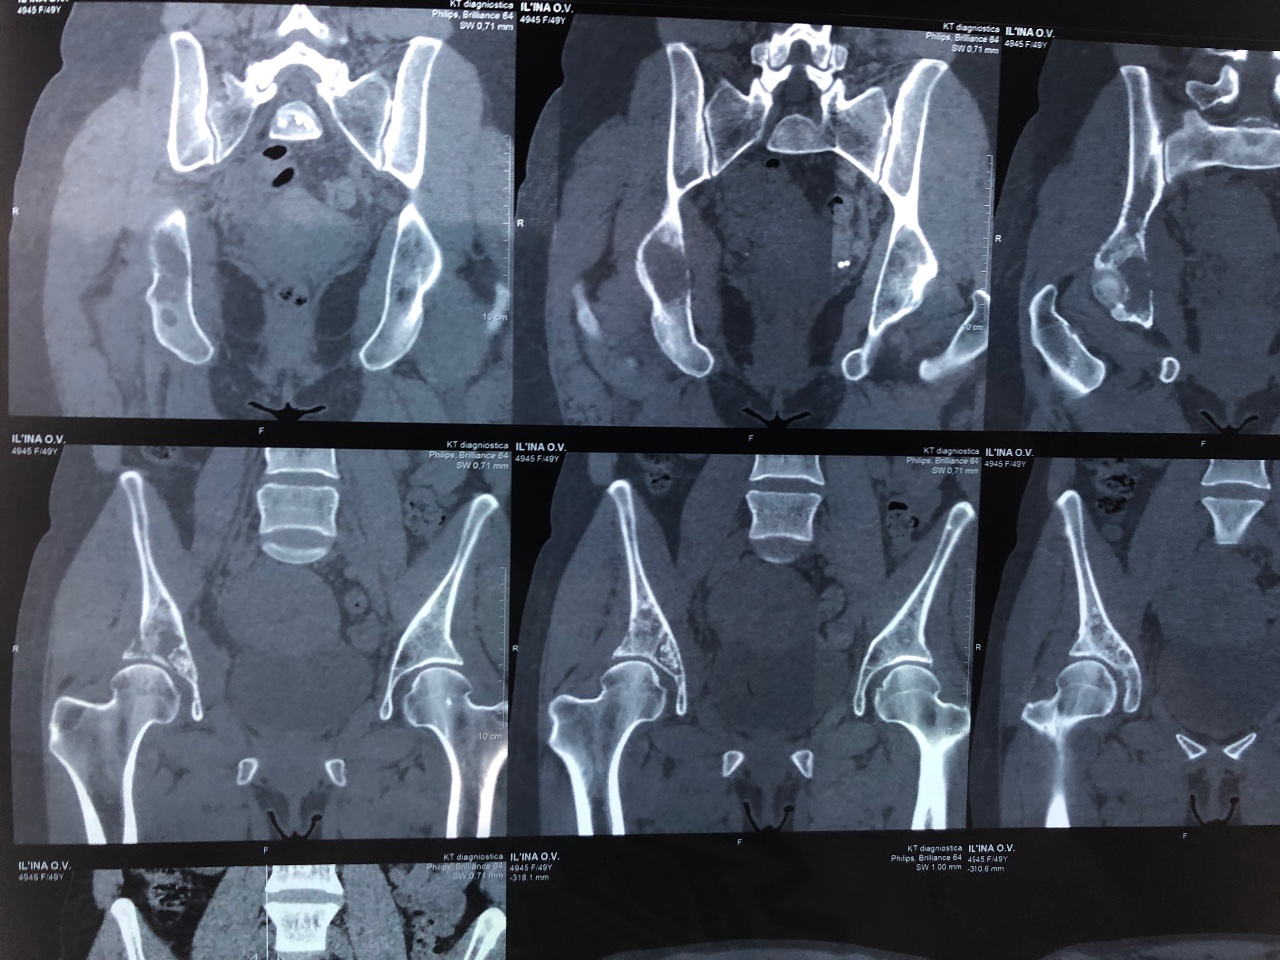

Компьютерная томография органов малого таза: оборудование и результаты исследований

Раздел: Галерея прозрений